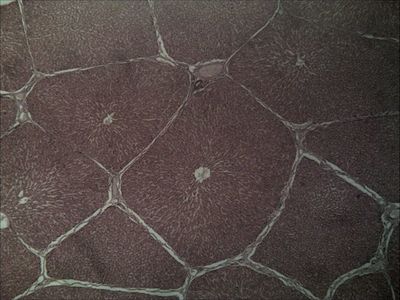

Question 1

Question

Identifique las estructuras indicadas en la imagen:

Answer

• Conducto biliar

• Rama de la vena porta

• Rama de la arteria hepática

• Vena central

• Capilar sinusoide

Question 2